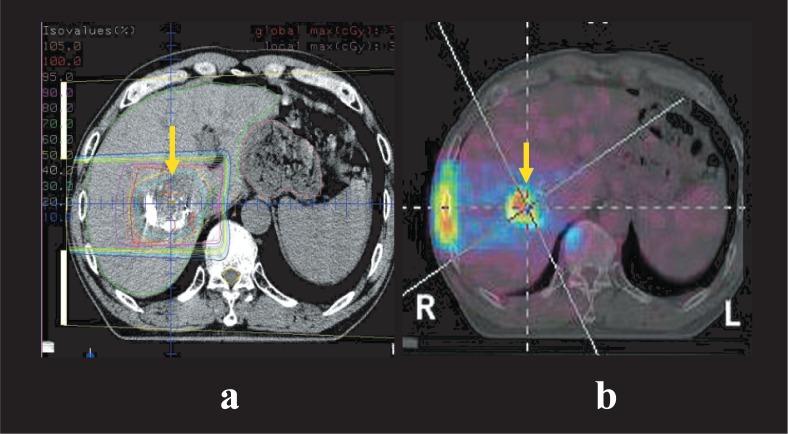

The Hyogo Ion Beam Medical Center was constructed in 2001 as the world's first charged particle radiotherapy center where both proton and carbon-ion radiotherapy can be performed. From April 2001 to February 2007, more than 1,400 patients with a variety of cancers were treated. Most of the tumors except for prostate cancer were considered hard to cure with standard treatments such as surgery or conventional x-ray radiotherapy. The clinical results obtained so far are very encouraging, mainly due to the excellent dose localization to the tumor and strong cell killing effects of protons and carbon-ions. The good indications are localized tumors including skull base tumors, head and neck tumors, cancers of the lung, the liver, and the prostate, and bone and soft tissue sarcomas. Charged particle radiotherapy will significantly improve the quality of life of cancer patients and promote their speedy return to normal lives or work if it is used for early stage cancer.

兵库离子束医疗中心于 2001 年建成,是世界上首个能够同时进行质子和碳离子放疗的重离子放疗中心。自 2001 年 4 月至 2007 年 2 月,已有 1400 多名患有各种癌症的患者接受了治疗。除前列腺癌外,大多数肿瘤都被认为难以通过手术或常规 X 射线放疗等标准治疗方法治愈。迄今为止获得的临床结果非常令人鼓舞,主要是由于质子和碳离子具有出色的肿瘤定位和强大的细胞杀伤作用。适应证为局限性肿瘤,包括颅底肿瘤、头颈部肿瘤、肺癌、肝癌和前列腺癌,以及骨和软组织肉瘤。如果将重离子放疗用于早期癌症,将显著提高癌症患者的生活质量,并促进他们尽快恢复正常生活或工作。